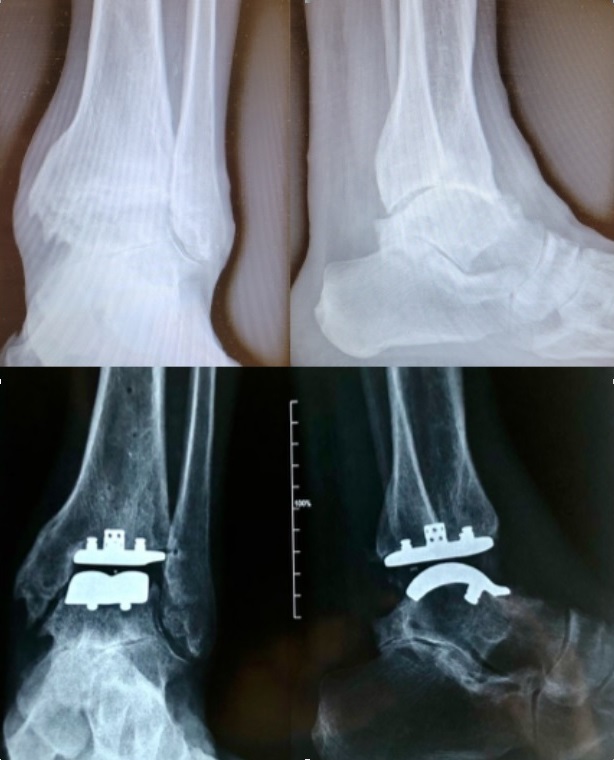

Radiografia dell'articolazione in un paziente prima e dopo l'impianto di una protesi di caviglia